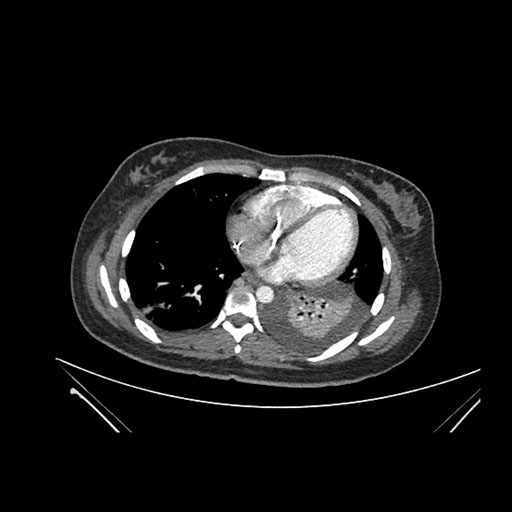

Axial Arterial

Axial Venous